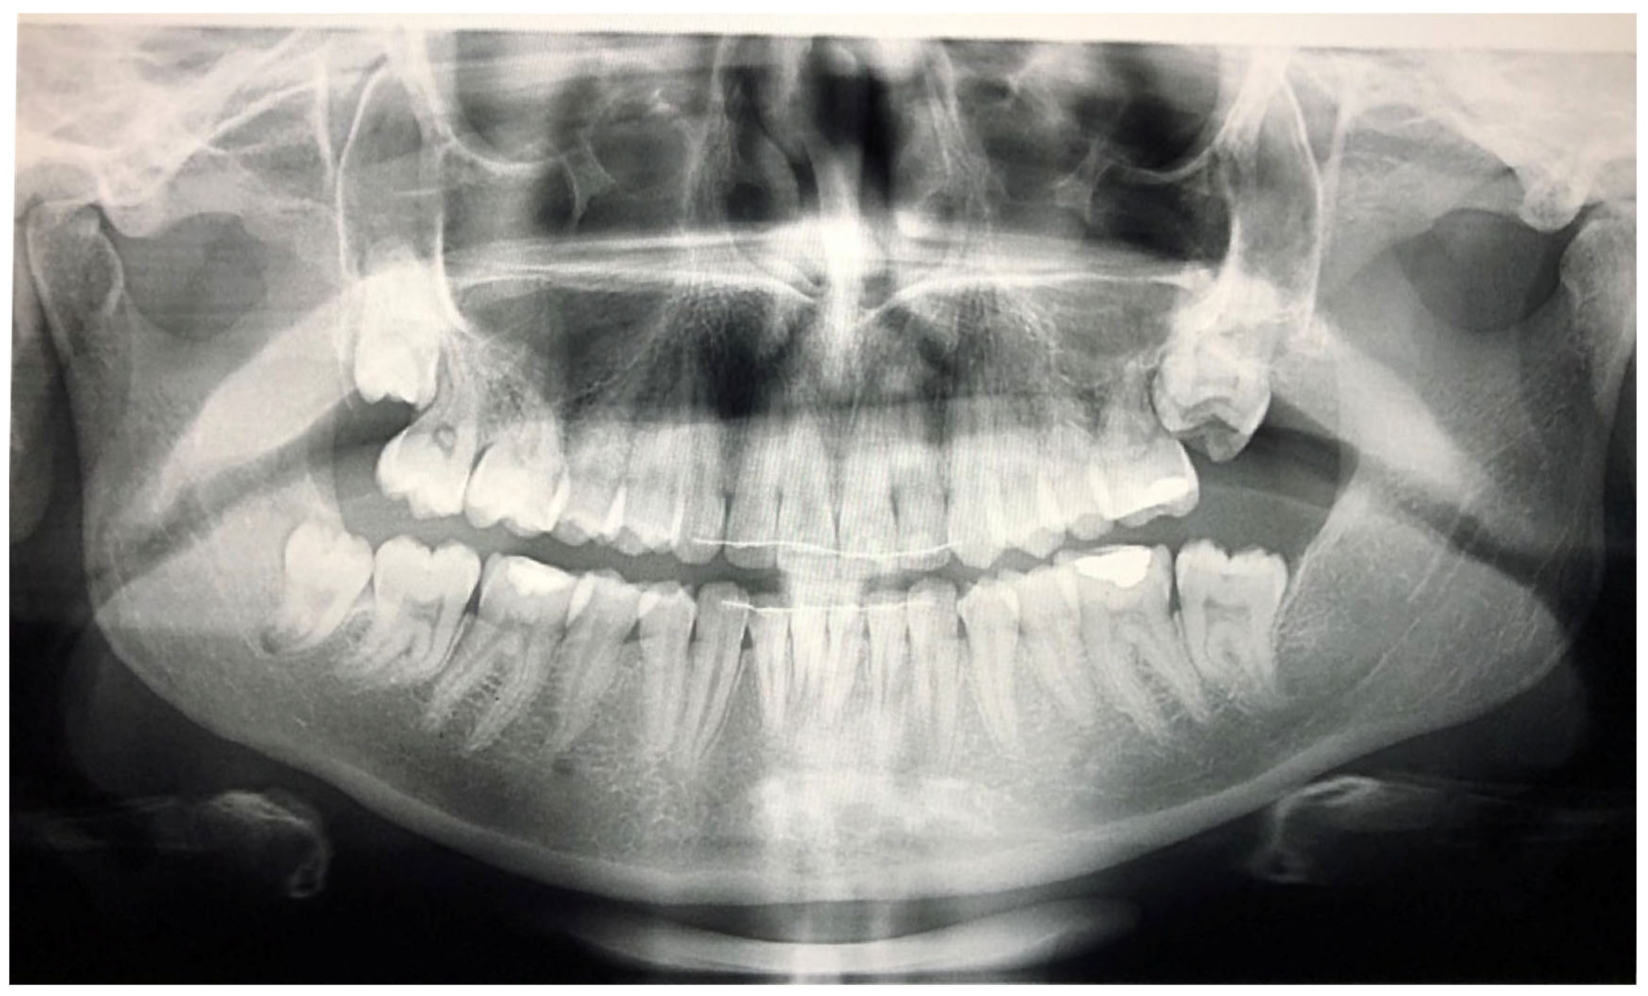

Figure 4.

Patient’s orthopantomography presenting Primary Failure of Eruption in all four dental quadrants.